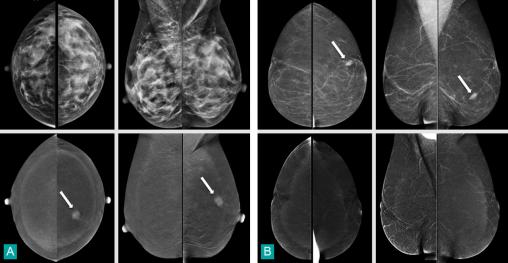

Mammographie : clichés du haut.Angiomammographie : clichés du bas.Chez la première patiente (fig. A), l'angiomammographie révèle la présence d'une masse rehaussée supéro-interne gauche (flèche), non décelable en mammographie en raison de l'hétérogénéité et de la densité glandulaire. L'échographie ciblée montre aisément une masse suspecte supéro-interne gauche qui, à la biopsie, révèle un carcinome canalaire infiltrant. Chez la secondepatiente (fig. 4B), l’angiomammographie permet de conclure que la masse dense ovalaire visible en mammographie dans le quadrant inféro-externe gauche (flèche) ne se rehausse pas, ce qui est en faveur de sa bénignité. La biopsie échoguidée conclut à une lésion de mastopathie fibreuse bénigne.